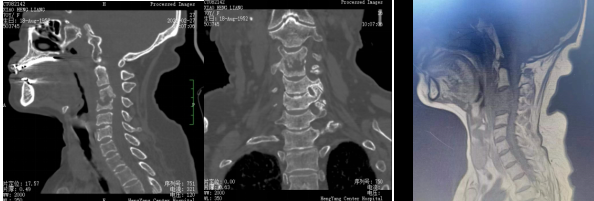

術(shù)前影像:C3、4椎體病變,椎管狹窄

患者入院后完善相關(guān)檢查,不查不知道,一查不簡單:患者頸椎疼痛不是簡單的肌肉勞損,而是頸椎骨頭出現(xiàn)了破壞、塌陷,神經(jīng)受壓。由于患者頸椎病變位置較高,骨質(zhì)破壞范圍較大,并后凸、脊髓受壓,椎體穩(wěn)定性差,稍有不慎容易出現(xiàn)災難性后果?,F(xiàn)有的重建材料難以達到好的臨床效果,蘇光輝主任團隊采用先進的3D打印技術(shù),為患者進行了個性化手術(shù)方案及假體設計,假體與需要切除骨質(zhì)完美匹配,最大程度恢復解剖結(jié)構(gòu)及重建的穩(wěn)定性,對假體進行骨小梁結(jié)構(gòu)設計,具有良好的骨長入效果,能夠減少假體下沉及松脫等術(shù)后并發(fā)癥的發(fā)生。